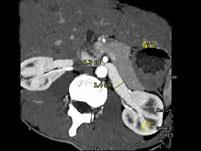

问题 女,24岁,发作性肉眼血尿1年,实验室检查:尿蛋白(-+)、红细胞(12/HP),尿蛋白直立试验(+),CT扫描如图,下列说法正确的是 ( )

选项 A.双肾大小形态正常 B.左肾静脉走行至肠系膜上动脉与腹主动脉间变细,近左肾处扩张 C.左侧肠系膜上动脉与腹主动脉夹角变小 D.左侧肠系膜上动脉与腹主动脉夹角增大 E.考虑为左肾静脉胡桃夹综合征

答案 ABCE